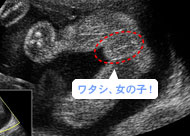

木(mùの葉みたいに、中央にラインが入っています。(妊娠23週)